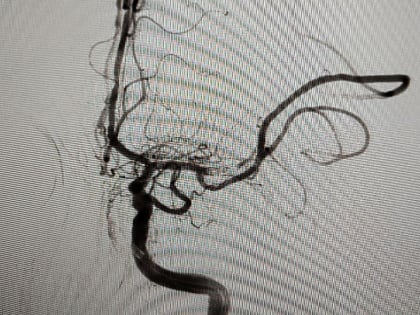

Фото: Официальный Телеграм-канал министра здравоохранения ЛНР Наталии Пащенко Врачи Луганской республиканской клинической больницы (ЛРКБ)  провели первые пять операций по эмболизации аневризмы головного мозга.